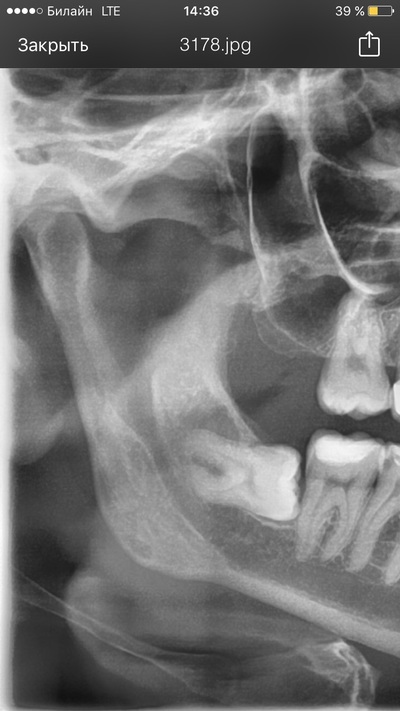

Посмотрите на снимки. Между верхним и нижним — разница в три недели. По ним хорошо заметно, что после удаления зачатков восьмёрок и «разблокировки», седьмые зубы сразу пошли в рост.